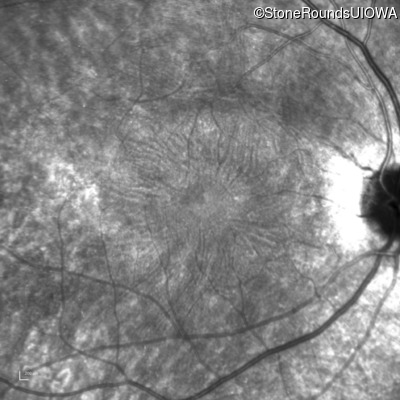

Infrared Fundus Photograph - Left -

20/20 -2

20/20